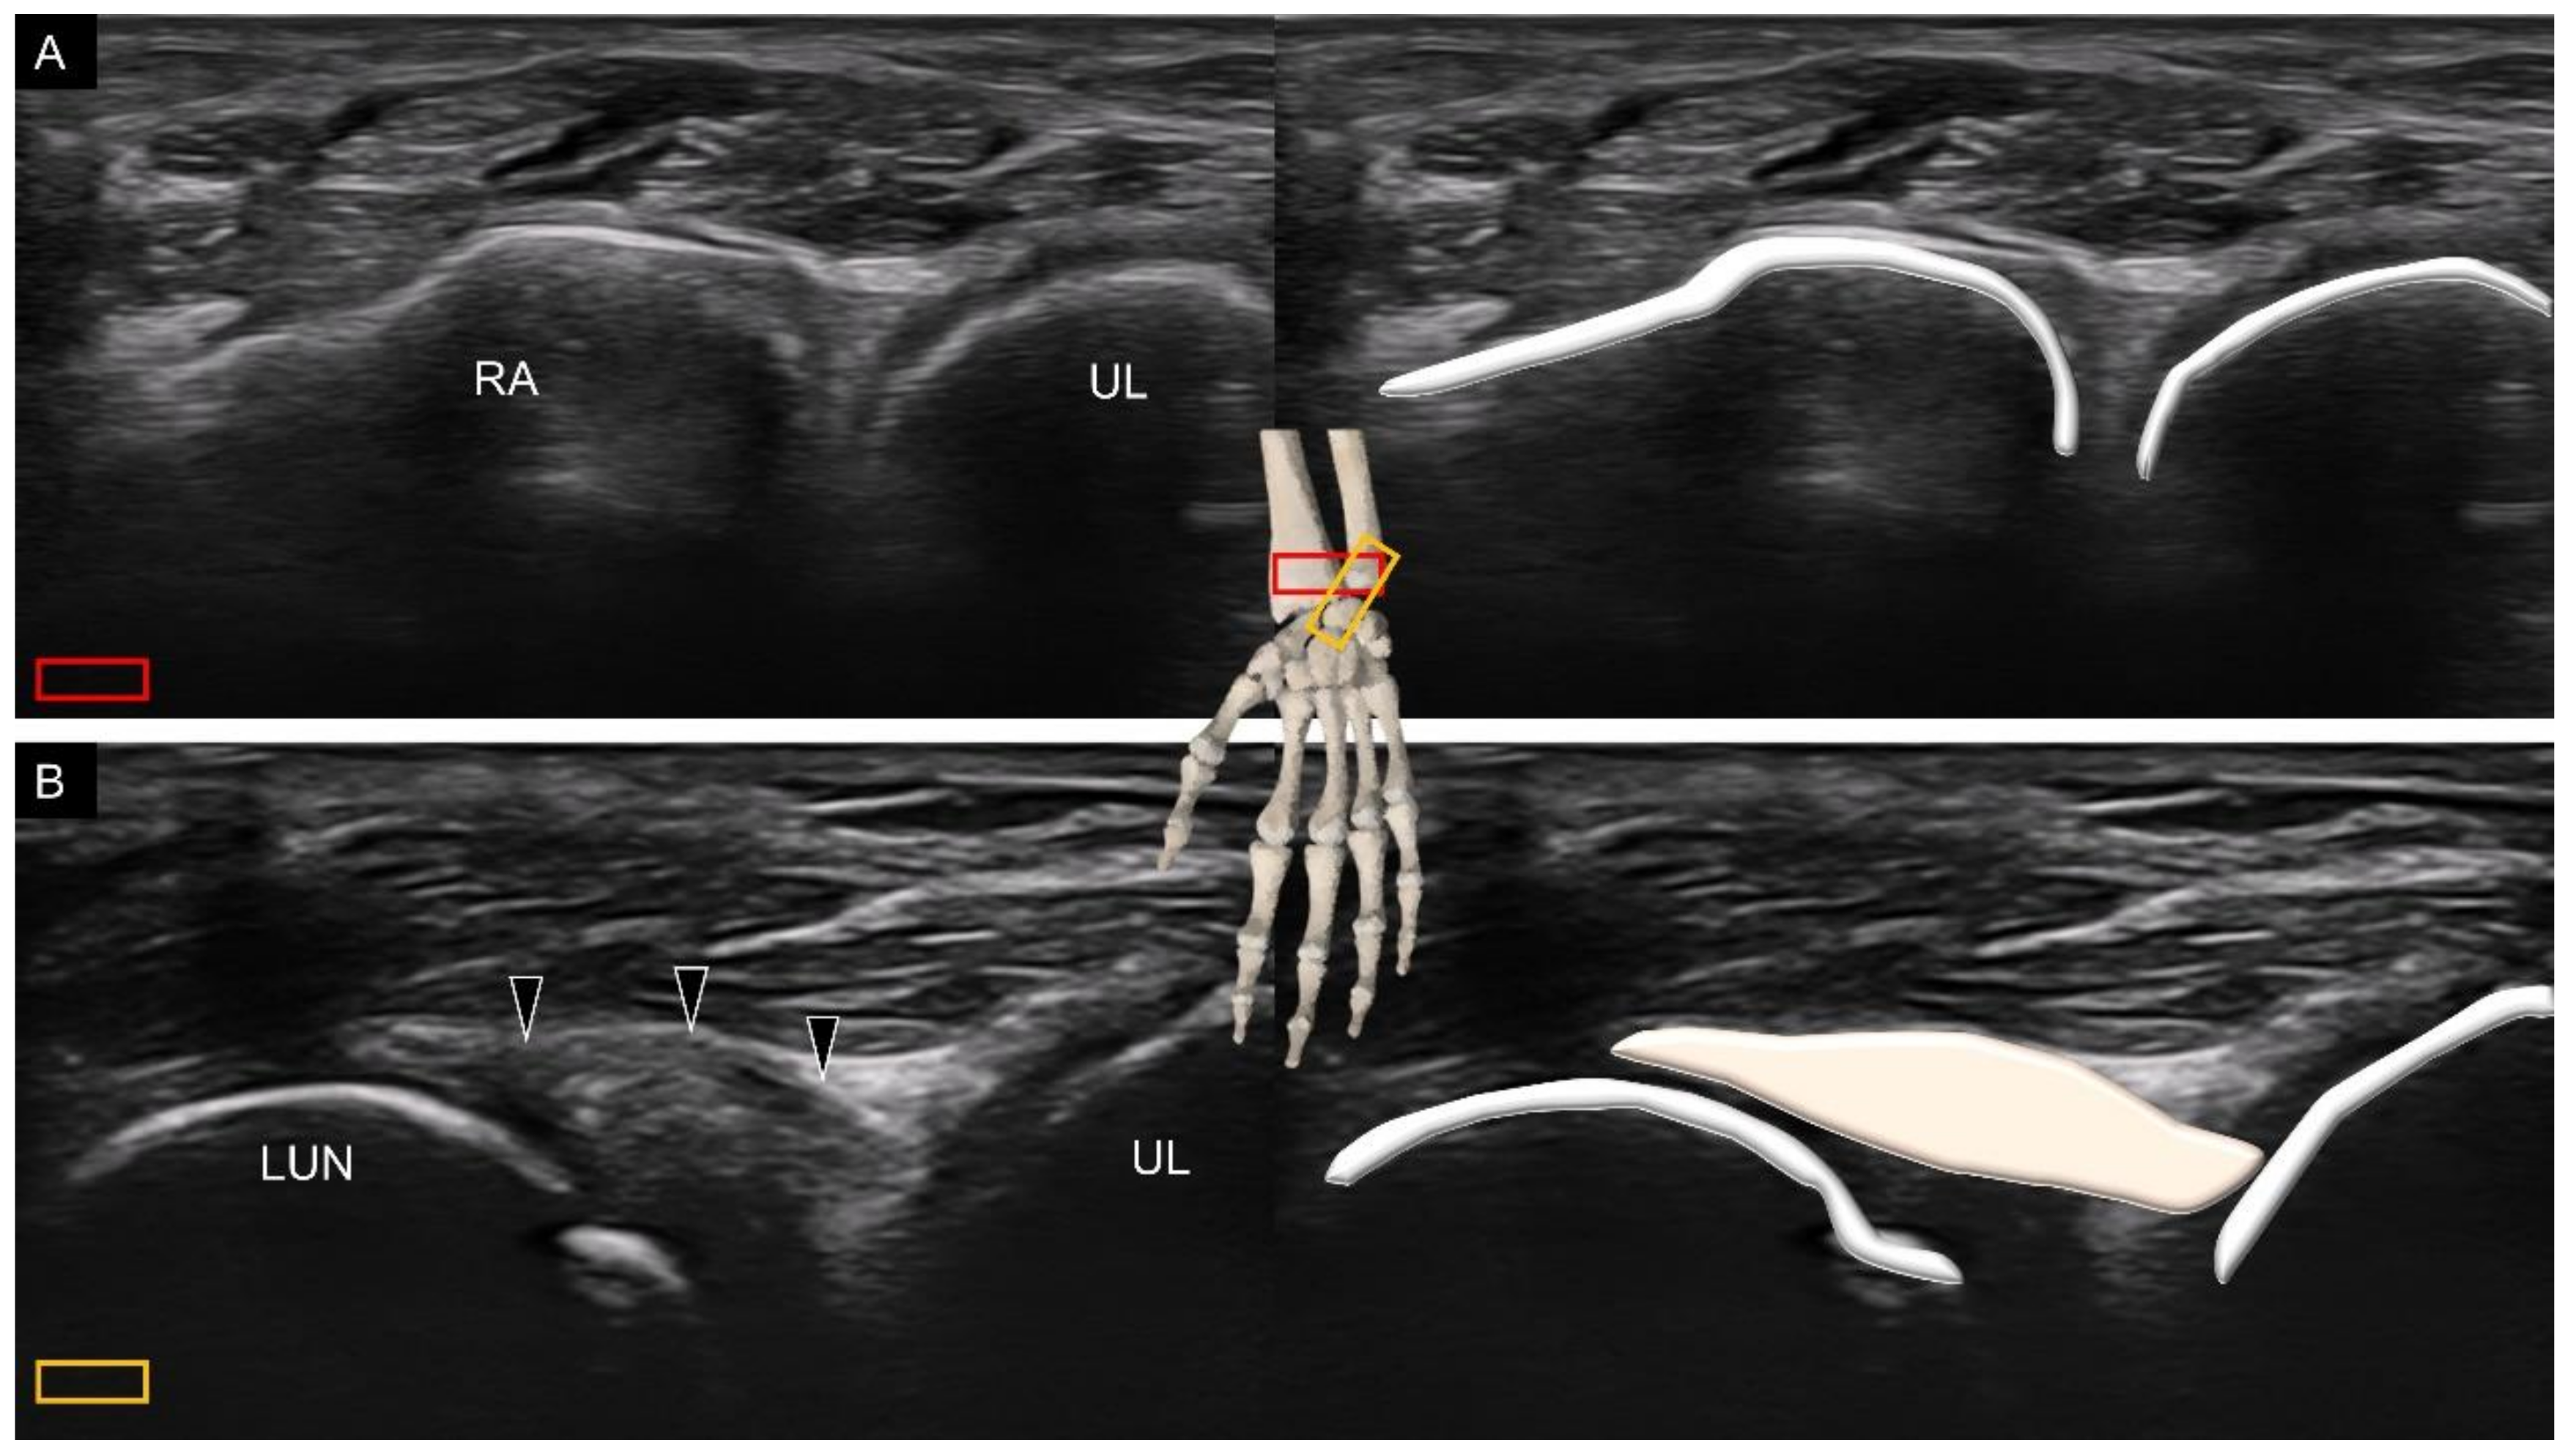

3.1. Attachment to the Capitate

5. Sonoanatomy of Dorsal Extrinsic Carpal Ligaments